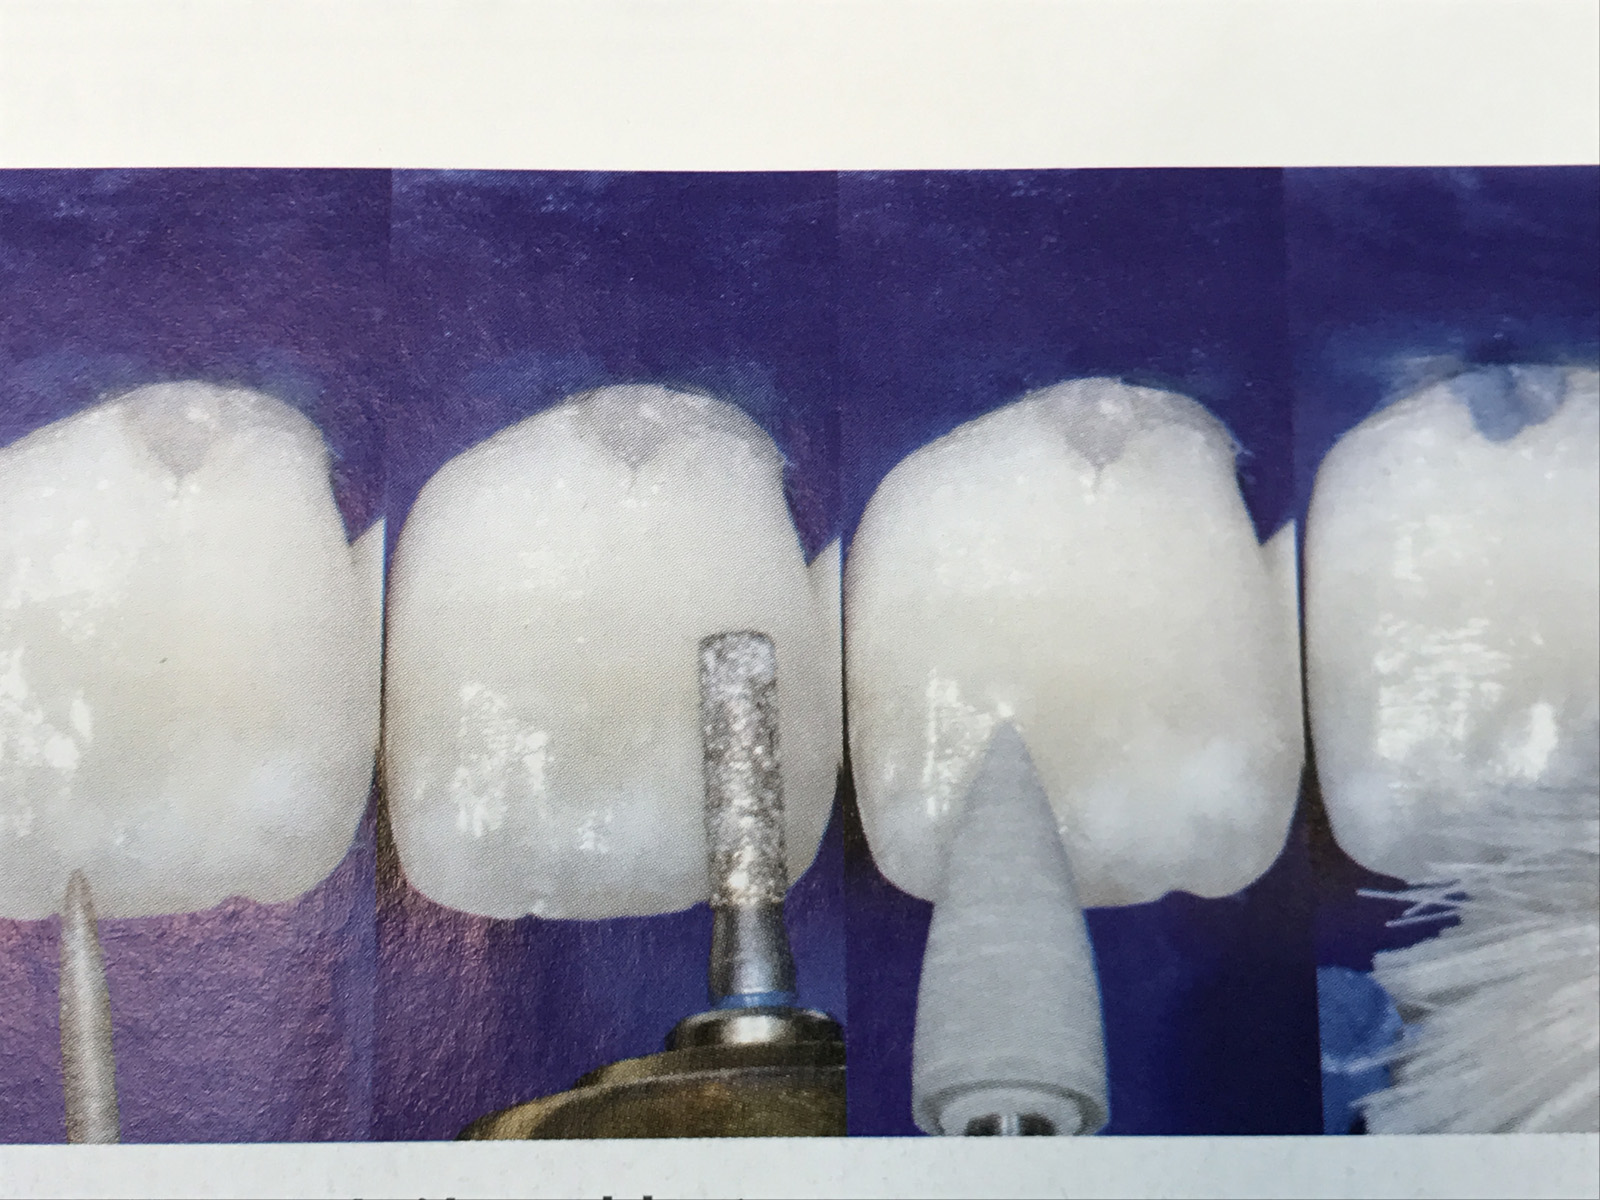

Frattura coronale conseguente ad un trauma sportivo.

Alla valutazione iniziale non è stata rivelata sintomatologia dolorosa di 2.1 e il dente ha risposto positivamente al test con cloruro di etile.

Dopo una valutazione clinica e radiografica si è deciso di ricostruire l'elemento dentario mediante una riabilitazione conservativa diretta con metodiche adesive utilizzando il sistema restaurativo di recente formulazione Venus Diamond.